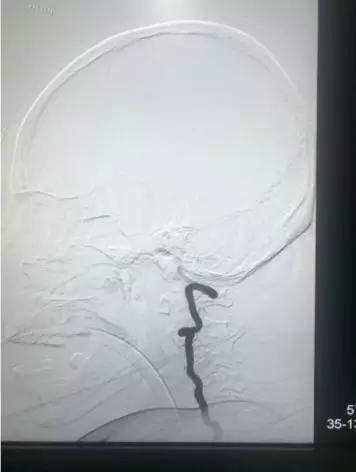

患者因树枝插在枕部无法平躺,给麻醉科带来极大困难。麻醉医生刘晓媛顶住压力侧卧位下插管成功。介入科刘健医生也是侧卧位下为患者进行了DSA实时血管造影,显示椎动脉未受到影响。

术中DSA造影显示:椎动脉位于树枝边缘,未受到影响